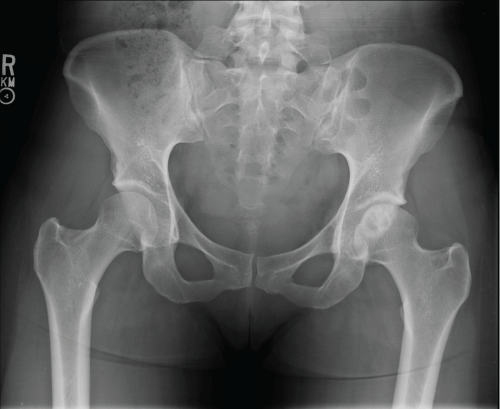

Case 1

MG is a 31 yo F who presented with left hip pain for over a decade. MRI and radiographs had been obtained prior to presentation to our office which showed anterior quadrant cystic changes in the femoral head consistent with AVN in the pre-collapse state. On physical exam, the patient had excellent range of motion. The patient had already tried and failed conservative measures such as oral pain control, CSI, and protected weight bearing. She elected to undergo core decompression of the affected femoral head. At one year postoperatively she has limited improvement in her pain and continues to rehabilitate Figure 1, Figure 2, Figure 3, Figure 4 and Figure 5.

Figure 2: Preoperative AP pelvis.View Figure 2

Figure 3: Preoperative coronal MRI. View Figure 3